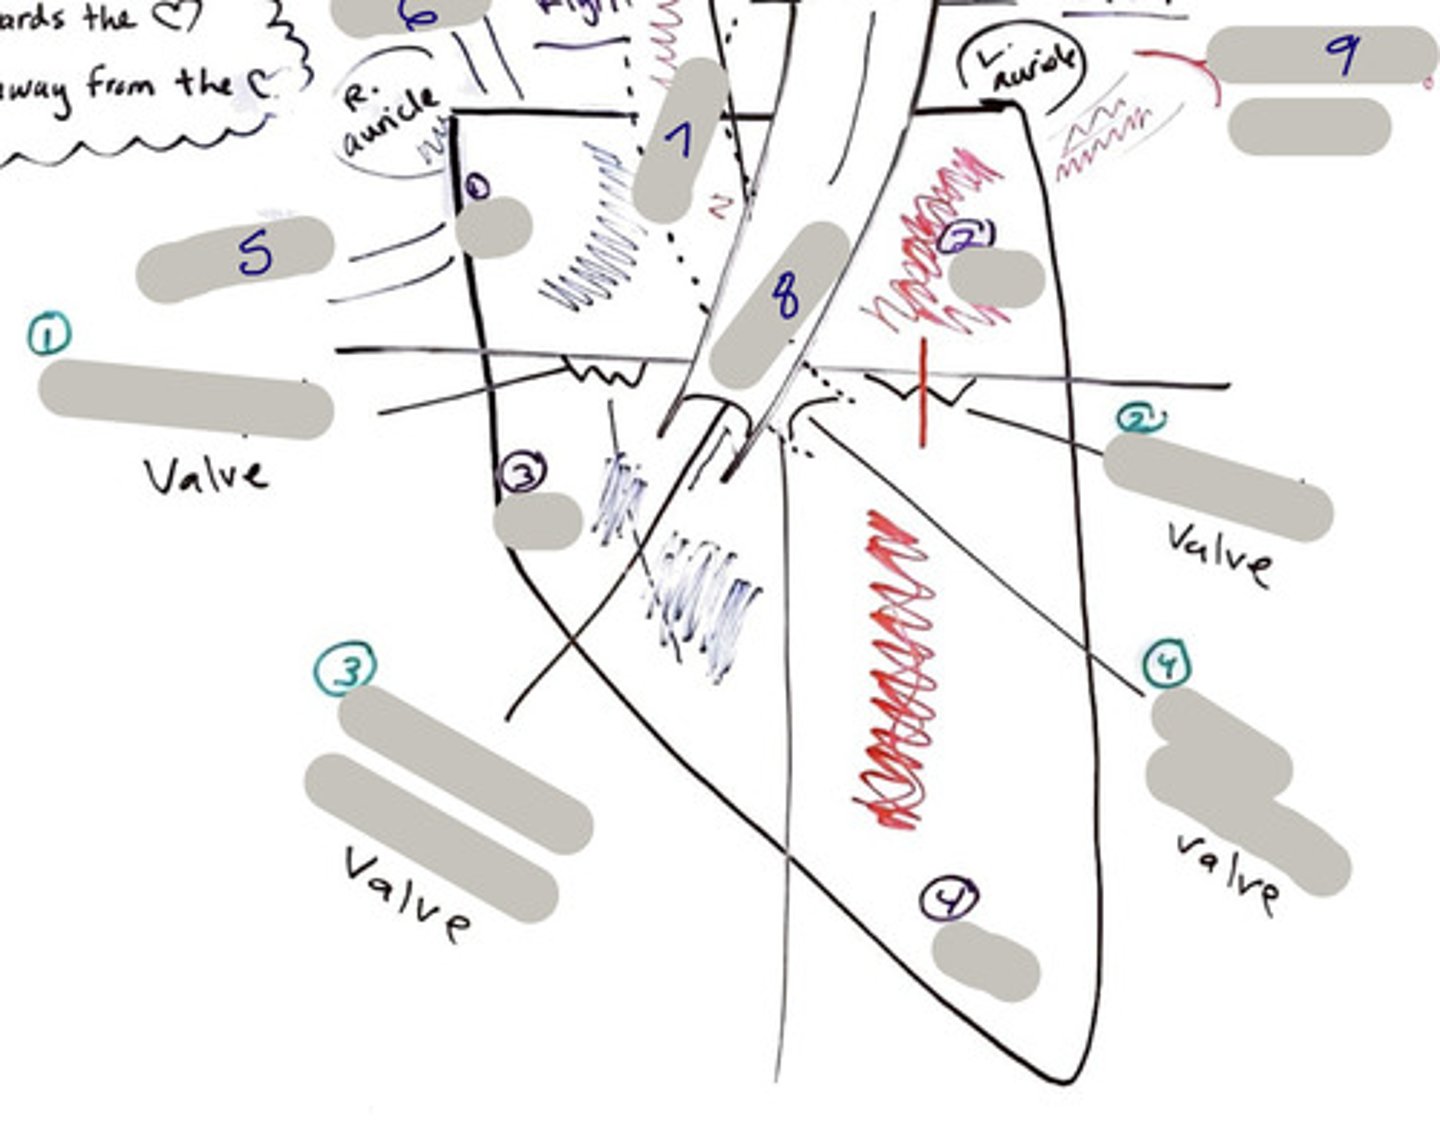

Tricuspid Valve (Right Atrioventricular Valve)

1-valve

Bicuspid valve (Left Atrioventricular Valve)

2-valve

Pulmonary Semilunar Valve

3-valve

Aortic Semilunar Valve

4-valve

Right Atrium

1-chamber

Left Atrium

2-chamber

Right Ventricle

3-chamber

Left Ventricle

4-chamber

Inferior Vena Cava

5-A vein that is the largest vein in the human body and returns blood to the right atrium of the heart from bodily parts below the diaphragm.

Superior Vena Cava

6-A vein that is the second largest vein in the human body and returns blood to the right atrium of the heart from the upper half of the body.

Aorta

7-The large arterial trunk that carries blood from the heart to be distributed by branch arteries through the body.

Pulmonary Trunk

8-carries blood from right ventricle to pulmonary arteries

Pulmonary veins

9-a vein carrying oxygenated blood from the lungs to the left atrium of the heart.